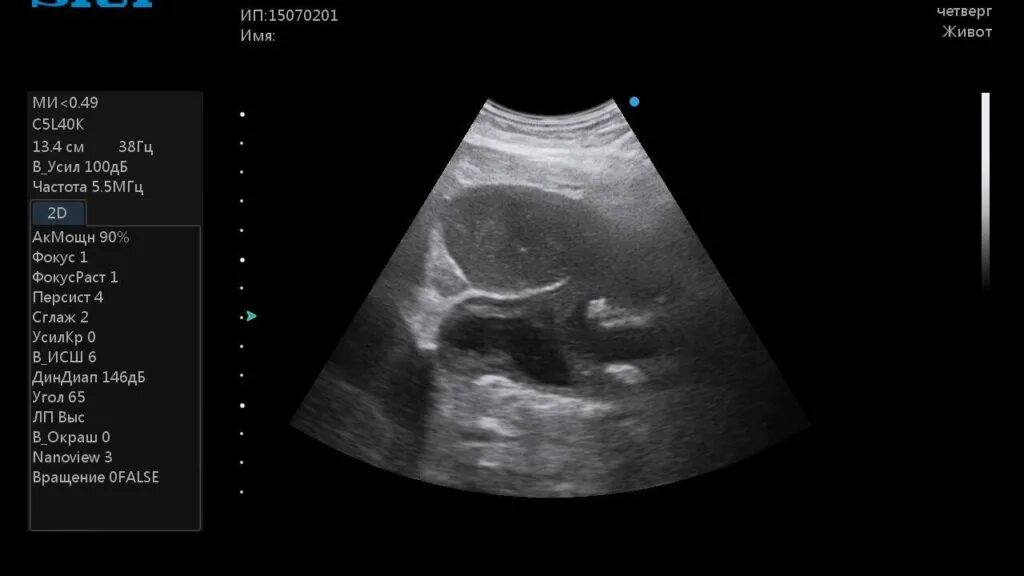

Как выглядит узи живота